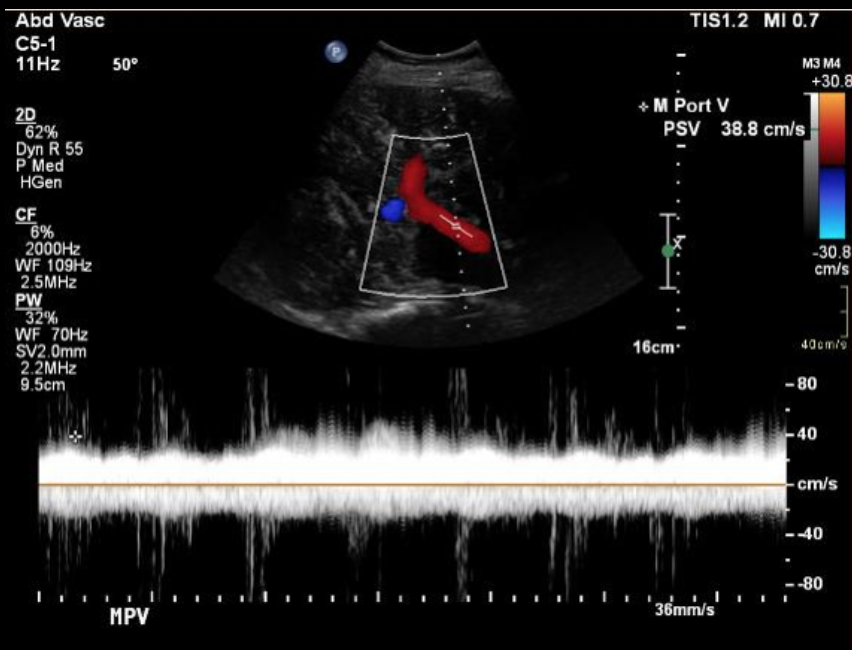

Portal Vein

• Normal Characteristics

• Hepatopetal flow (toward the liver)

• Antegrade (above the line)

• Can have gentile undulations (wavy appearance)

• Normal velocity = 16-40